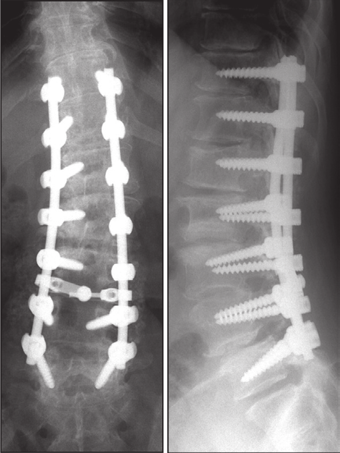

3.降低内固定硬度和减少融合区内固定数量

(1)降低内固定棒的硬度,用钛合金代替钴铬合金棒;

(2)全节段椎弓根螺钉固定改用间隔置钉固定;

(3)适当降低固定融合区内固定强度。

图25 降低内固定硬度和减少融合区内固定数量